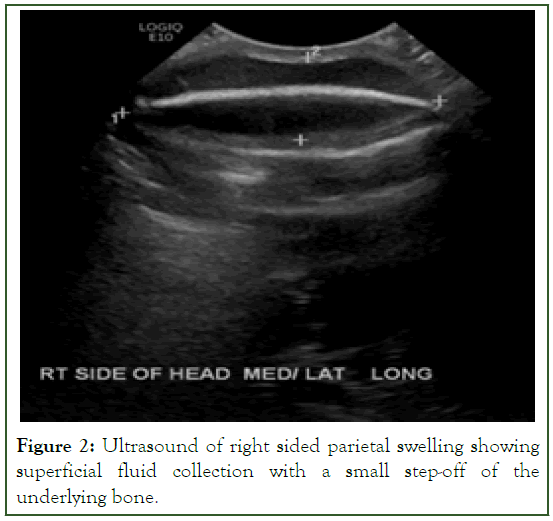

A skeletal survey showed no fractures, thinning of bones or rachitic changes. A repeated TSH level indicated an increase to 45.440 uIU/mL. A reassessment ultrasound of the scalp cystic lesion showed a superficial fluid collection with a small step-off of the underlying bone (Figure 2).

Figure 2: Ultrasound of right sided parietal swelling showing superficial fluid collection with a small step-off of the underlying bone.